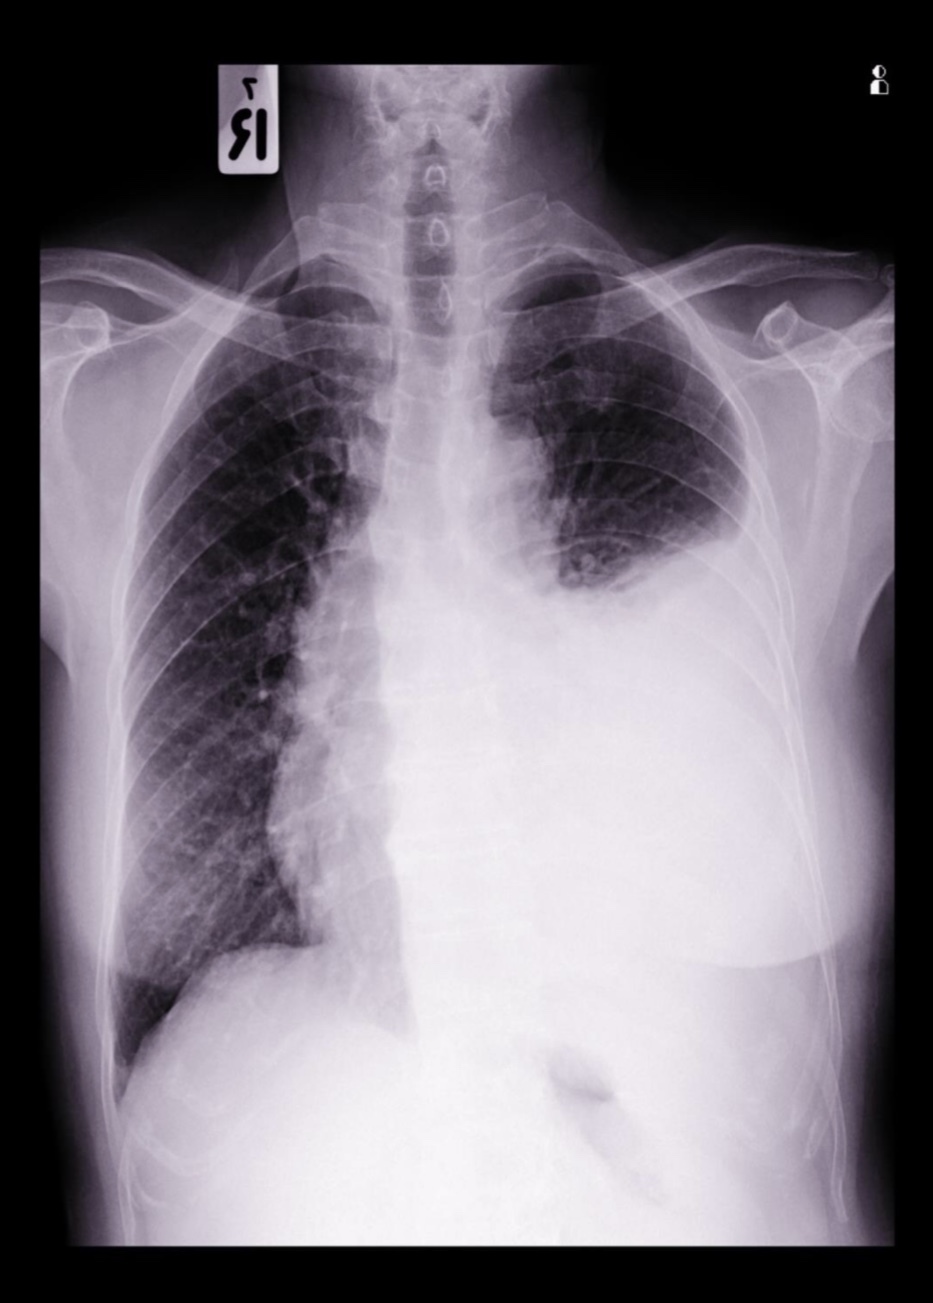

Unilateral pleural effusion

Right pneumonectomy (there are clips)

Without clips it would be right lung collapse

Right lower lobe collapse

Right lower lobectomy